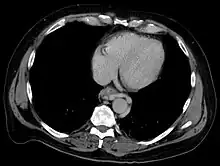

The upper two thirds of the esophagus are drained via the esophageal veins, which carry deoxygenated blood from the esophagus to the azygos vein, which in turn drains directly into the superior vena cava. These veins have no part in the development of esophageal varices. The lower one third of the esophagus is drained into the superficial veins lining the esophageal mucosa, which drain into the left gastric vein, which in turn drains directly into the portal vein. These superficial veins (normally only approximately 1 mm in diameter) become distended up to 1–2 cm in diameter in association with portal hypertension.

Normal portal pressure is approximately 9 mmHg compared to an inferior vena cava pressure of 2–6 mmHg. This creates a normal pressure gradient of 3–7 mmHg. If the portal pressure rises above 12 mmHg, this gradient rises to 7–10 mmHg.[5] A gradient greater than 5 mmHg is considered portal hypertension. At gradients greater than 10 mmHg, blood flowing through the hepatic portal system is redirected from the liver into areas with lower venous pressures. This means that collateral circulation develops in the lower esophagus, abdominal wall, stomach, and rectum. The small blood vessels in these areas become distended, becoming more thin-walled, and appear as varicosities.

In situations where portal pressures increase, such as with cirrhosis, there is dilation of veins in the anastomosis, leading to esophageal varices.[6] Splenic vein thrombosis is a rare condition that causes esophageal varices without a raised portal pressure. Splenectomy can cure the variceal bleeding due to splenic vein thrombosis.